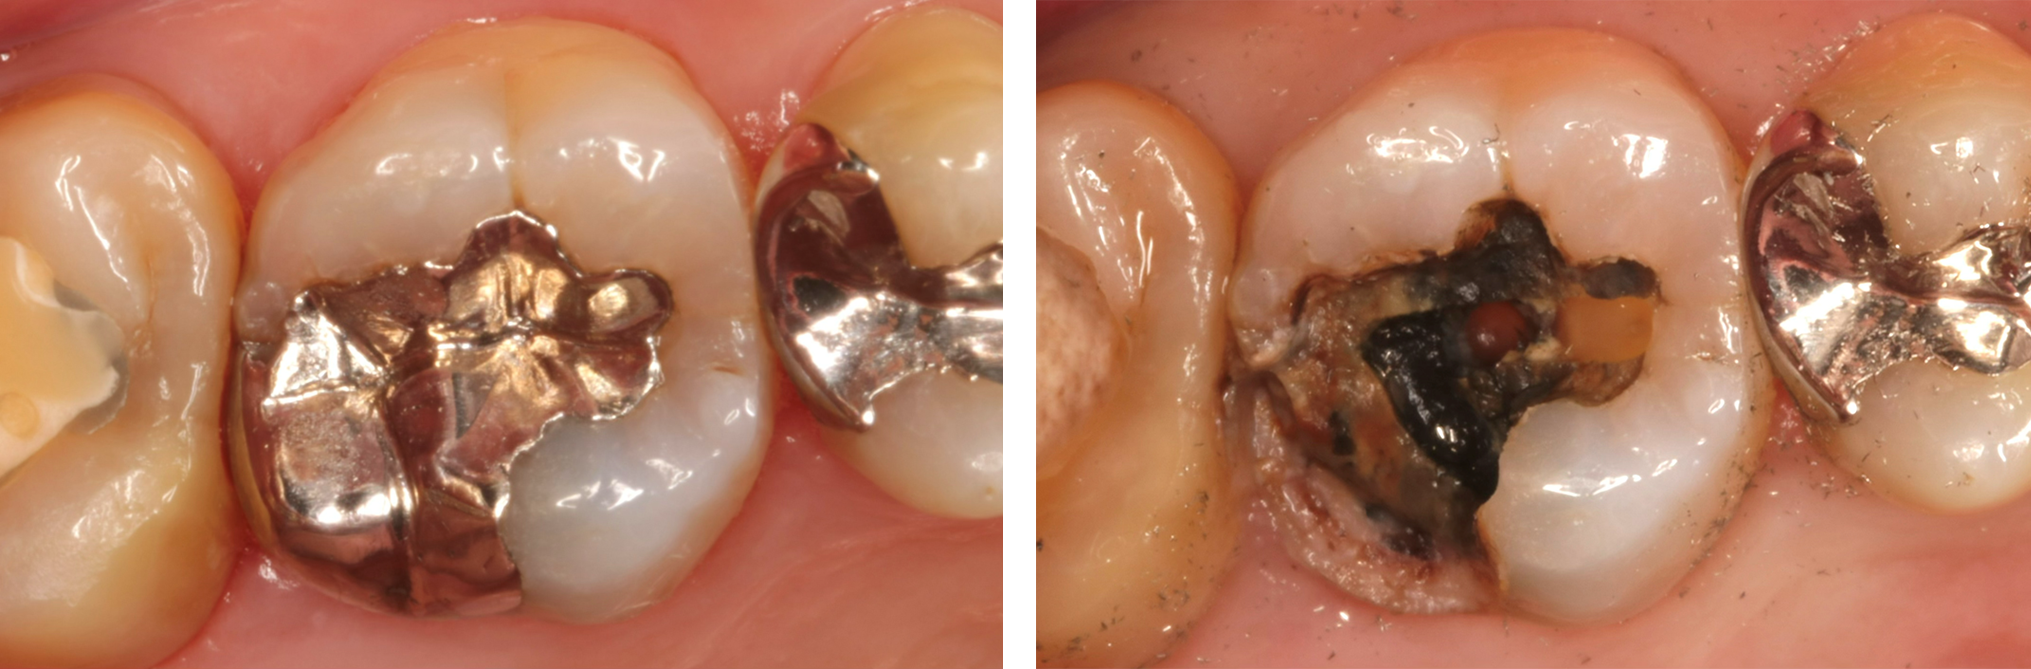

根管治療を行う際は、基本的に入っている詰め物や被せ物は一旦全て取り除いてから行います。被せ物(特に金属の被せ物)の下はX線画像では映らない虫歯が残っている可能性があり、それが原因で歯の中に細菌が入ってきている可能性があるので、それらを取り除く必要があります。

レントゲンでは明らかな虫歯が確認できないですが

はずしてみると、中は虫歯(薬液で青く染まる)で汚染されていて、根管の中まで感染していました。そしてそのう蝕を全て取り除き、根管に器具が入れられる必要最小限の穴を開けていきます(髄腔開拡)。